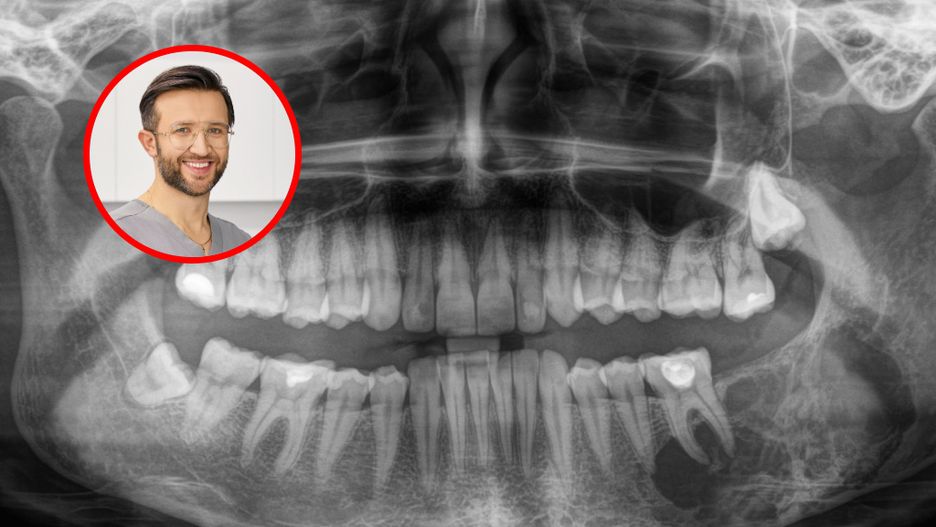

Wykryta zmiana nowotworowa w szczęce podczas wizyty u ortodontyWykryta zmiana nowotworowa w szczęce podczas wizyty u ortodonty

Źródło zdjęć: © Dr Cićkiewicz

Wizyta u ortodonty kojarzy się głównie z prostowaniem zębów. Tymczasem zanim pojawi się aparat stały, standardem są badania diagnostyczne: zdjęcie pantomograficzne (panoramiczne), cefalometryczne, a w wybranych przypadkach tomografia CBCT. To właśnie na takich obrazach czasem wychodzą zmiany, o których pacjent nie miał pojęcia - od torbieli w kości, przez patologie zatok, aż po sygnały problemów naczyniowych, które wymagają pilnej konsultacji lekarskiej. O jednym z takich przypadków opowiada w rozmowie z WP abcZdrowie dr n. med. Maciej Cićkiewicz, ortodonta z ponad 20-letnim doświadczeniem i właściciel Cićkiewicz Clinic.

- Mieliśmy kiedyś pacjentkę, która chciała założyć aparat ortodontyczny. Wykonaliśmy pantomogram, który następnie rozszerzyliśmy o zdjęcie radiologiczne 3D i zaniepokoiła nas pewna zmiana w kości, dlatego pacjentkę skierowaliśmy na dalsze badania i do specjalistów. Potwierdziły się nasze obawy o zmianie nowotworowej, a pacjentka wróciła na leczenie ortodontyczne już z wyciętym fragmentem żuchwy i przeszczepionym fragmentem kości z nogi. Zmiany zostały wycięte na czas, dlatego zachowanie czujności, nawet kiedy niepokojące symptomy zupełnie nie dotyczą naszej dziedziny, jest kluczowe.